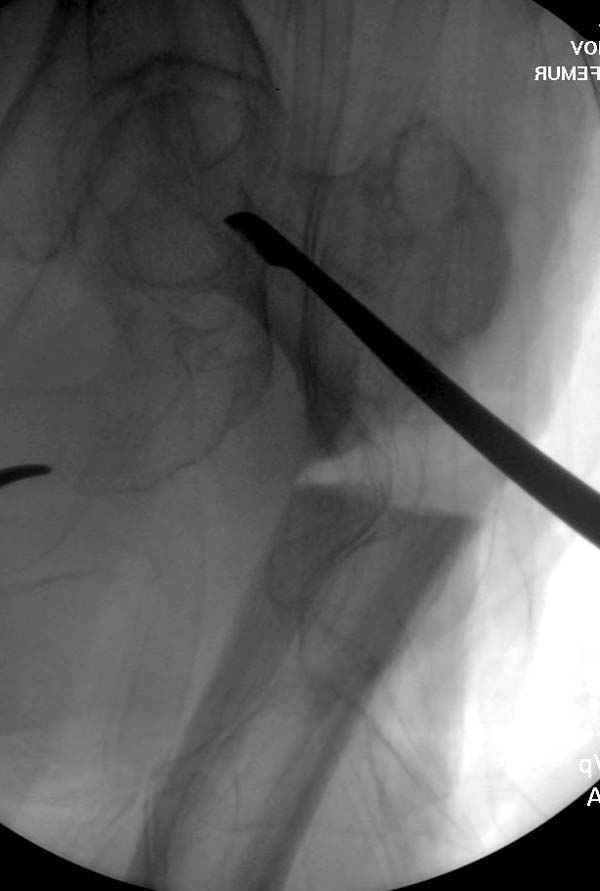

Re: Ятрогенный подвертельный перелом

Не стали усложнять интрамедуллярным вариантом коррекции, легче контролировать коррекцию пластиной, поэтому сделали операцию 95 градусной Blade Plate, разогнув до 110 градусов.

Надеемся на успех, потому что до введения пластины дефект от импланта забили костной стружкой и удалось создать компрессию между отломками, максимальную для импланта (150 кило/паунд). Сделана дополнительная костная пластика и за счет измененного угла пластины устранено укорочение конечности.

Страйкер предоставил отличный инструмент - крючок для удаления длинного гвоздя. Считаем, что врачебная ошибка по установке привела к несостоятельности импланта и к ятрогенному осложнению.